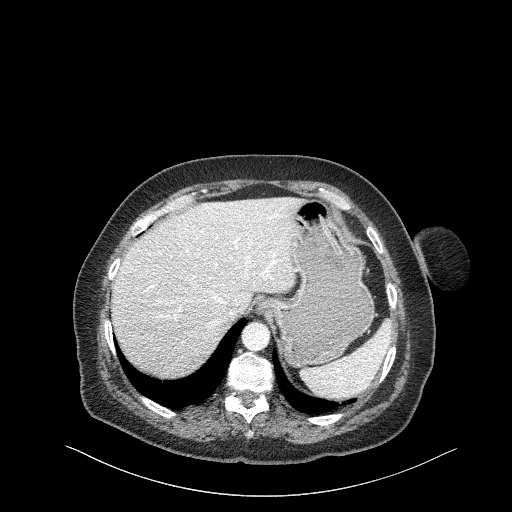

Generated VENOUS CT scan (A→B translation)

Full window (WL 1023.5, WW 4095 β†’ Low βˆ’1024, High +3071)

Actual HU range: [-242.2, 411.7]

Lung window (WL -600, WW 1500 β†’ Low βˆ’1350, High +150)

Actual HU range: [-242.2, 150.0]